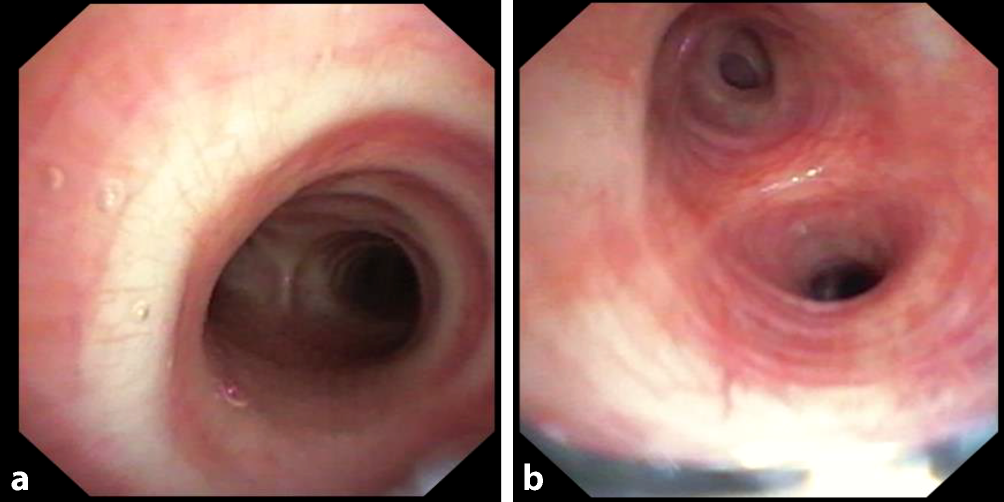

Die weiteren diagnostischen Schritte erfolgten zur Bestätigung der vorliegenden Exposition gegenüber Vogelprotein (Tab. 2) sowie zum Ausschluss weiterer Differenzialdiagnosen. In der Bronchoskopie zeigte sich als zusätzlicher suggestiver Marker ein verminderter Quotient (< 1) von CD4/CD8-Zellen in der bronchoalveolären Lavage. Makroskopisch zeigte sich zudem eine ubiquitär entzündete bronchiale Schleimhaut (Abb. 3).

Abb. 3

Bronchoskopie am 3. stationären Tag mit Sicht auf die Karina (a) und nach Abgang der Karina (b)